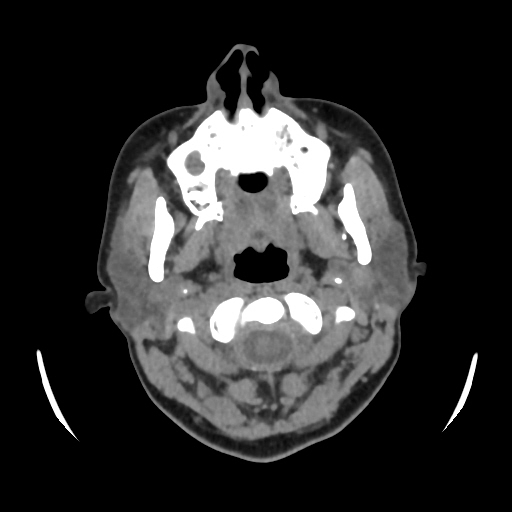

A 33 years old woman with protruding eyeballs & hyperthyroidism since 2 years